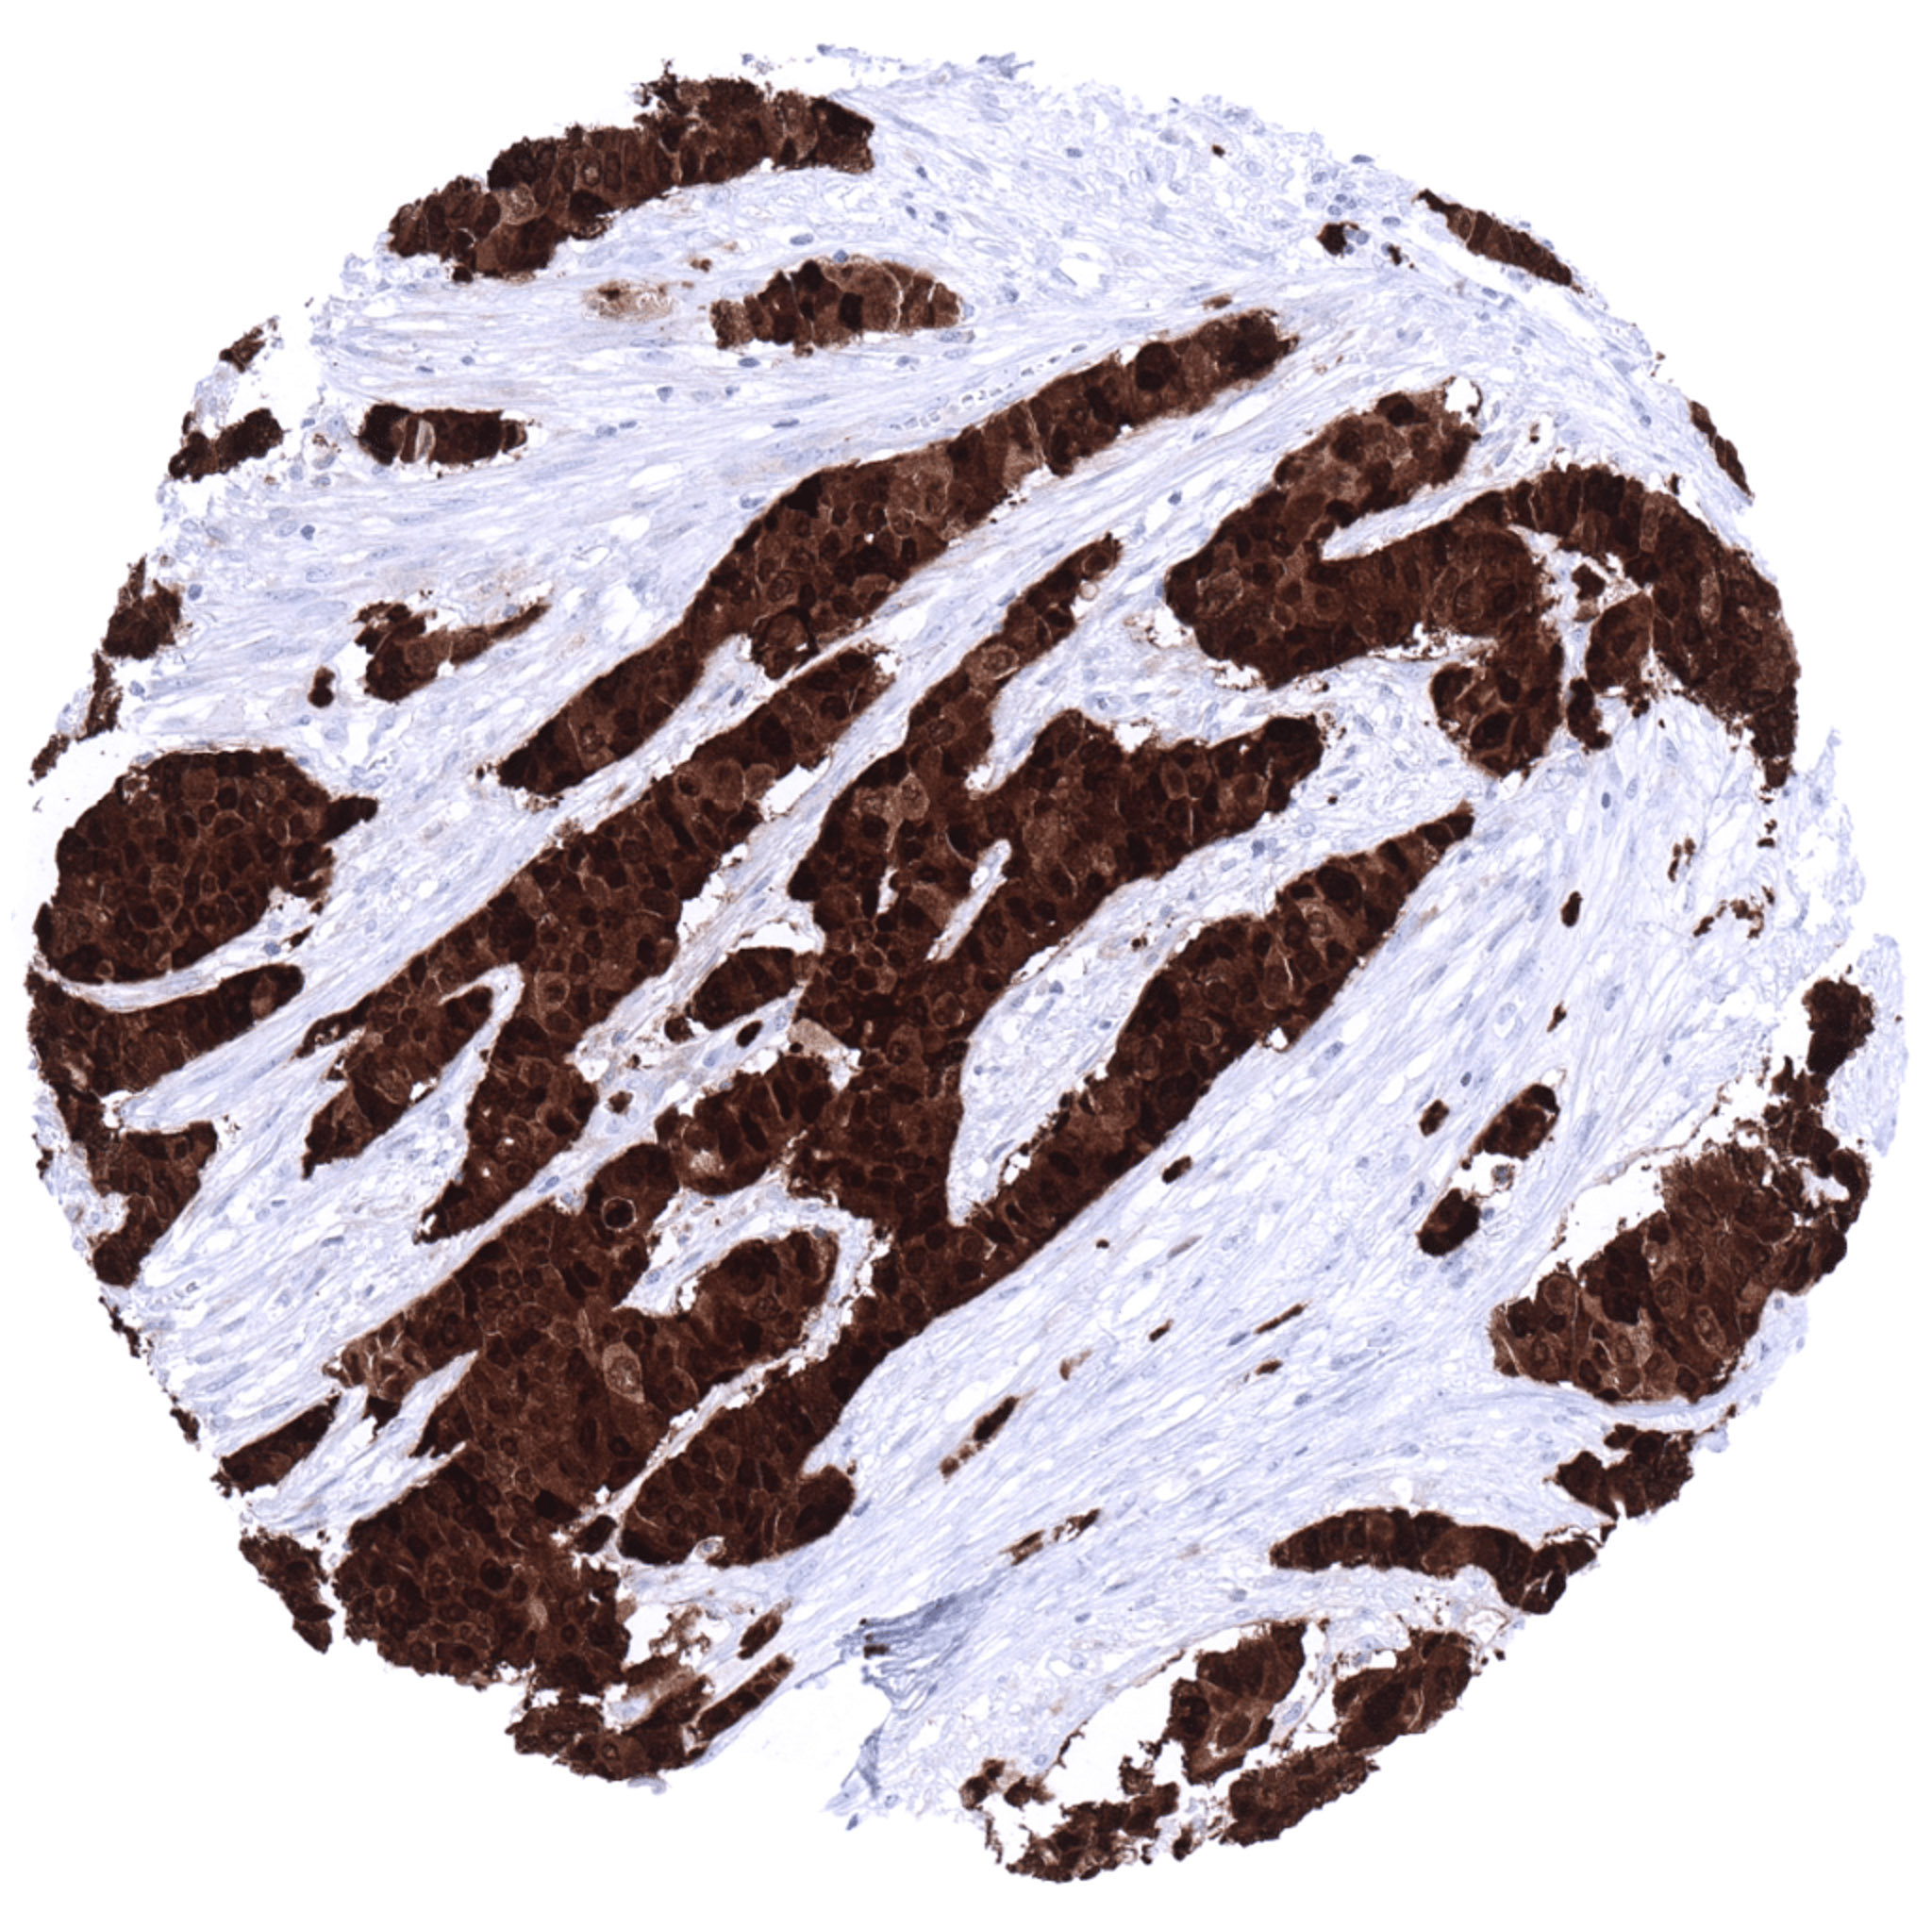

Urinary bladder- Muscle-invasive urothelial carcinoma with strong S100P immunostaining of tumor cells.